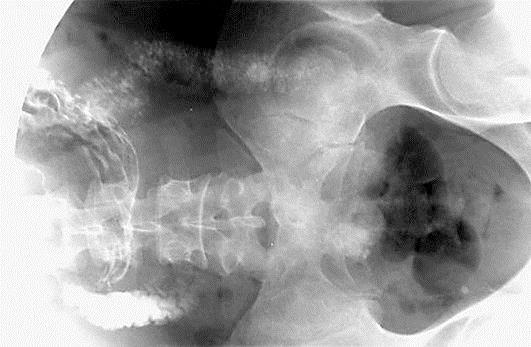

We present 2 cases of SBS treated with STEP. Enterectomy was performed for massive intestinal ischemia secondary to a gastrointestinal stromal tumor in the first case and to catastrophic antiphospholipid syndrome in the second. After enterectomy, the short residual bowel measured 34 cm in the first patient and 45 cm in the second. In both cases STEP, cholecystectomy, and gastrostomy were performed. In the first case a Brooke neovalve was created, and in the other the ileocecal valve was preserved.

我们呈现2例接受STEP治疗的SBS病例。第一例因胃肠道间质瘤继发大面积肠缺血行肠切除术,第二例因灾难性抗磷脂综合征行肠切除术。肠切除术后,第一例患者剩余短肠长度为34 cm,第二例为45 cm。两例均行STEP、胆囊切除术及胃造口术。第一例创建了布鲁克新瓣,另一例保留了回盲瓣。